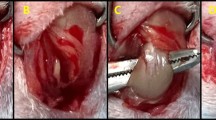

Animal treatment

Adult male (8 weeks old) Sprague–Dawley (SD) rats were used and all animal care procedures were approved by laboratory animals of the Fifth Affiliated Hospital of Wenzhou Medical College. SD rats were fed under a stable raising condition and then divided into three groups randomly. For sham control, rats were anesthetized with 3% pentobarbital natrium (0.1 mL/10 g, Sigma, P3761). Then, a 1-cm deltoid incision was performed and the rotator cuff was identified. After that, the deltoid muscle and skin were closed. In the tendon transection surgery group, which was defined as the muscle cutoff group in this study, tendons of supraspinatus were completely transected and 5-mm-long tendons at each supraspinatus were removed in order to prevent tendon reattachment. Then, the incision of muscle and skin was closed. There were at least eight rats in each group. Postoperatively, the sham control was fed with standard chow diet and the tendon transection surgery group was fed with standard chow diet and 5% leucine-containing diet (Sigma, 61,820) respectively for 2 weeks. Both the standard chow and leucine-rich diet that were prepared according to previous studies were semi-purified and isocaloric diets (Cruz and Gomes-Marcondes 2014; Viana and Gomes-Marcondes 2013). Standard chow diets contained 18% protein and leucine-rich diets contained 18% protein plus 5% l-leucine, which represented a high percentage of this amino acid. Besides, both diets contained 70% carbohydrates (sucrose, starch and dextrin), 7% fat (soybean oil) and 5% fiber (micro-cellulose purified) accompanied by a mixture of vitamins, minerals, cysteine and choline. The standard chow and the leucine-rich diets contained 2% and 5% l-leucine, respectively. For inhibitor treatment, the established RCT rat model was treated with a tail intravenous injection of LY294002 (0.25 mg/100 g, PI3K inhibitor, Beyotime, S1737) and Rapamycin (0.1 mg/100 g, mTOR inhibitor, MCE, HY-10219) for 2 weeks. LY294002 and Rapamycin were diluted by PBS and the other three groups were treated with a tail intravenous injection of isometric vehicle (PBS).

Muscle harvest

Two weeks after surgery and treatment, SD rats were anesthetized and decapitated. Then, a 3–4-cm incision was performed longitudinally and the supraspinatus was harvested carefully. The wet weight of the supraspinatus was processed immediately after removing the tendon and scar tissue. Supraspinatus tissues were divided into three parts and frozen for the follow-on experiments.

Histologic analysis

Muscle tissues were cut into a reasonable size (0.5–1 cm) and processed 4% phosphate-buffered paraformaldehyde-fixed for more than 24 h. After paraffin embedding, a 4-μm paraffin section was stained with hematoxylin and eosin stain (Solarbio, A8090) according to a previous study (Kim et al. 2012). The morphology and histology of the supraspinatus were identified through a microscope and analyzed utilizing ImageJ and Adobe Illustrator CS4 software.

Leucine rescues tendon transection-induced muscle pathological changes and cell apoptosis

Muscle pathological changes were evaluated with H&E-stained histology; atrophic muscle fibers, fatty infiltration and inflammatory cell infiltration were observed in the tendon transection group feeding with normal diet (Fig. 2a, b). When administrated with leucine in the tendon transection group, there was a significant decrease in the number of inflammatory cells, fat accumulation, the degree of muscle fiber degeneration and fiber cross-sectional area (Fig. 2a–c). Since tendon transection could cause myopathy, we speculated there should have been an occurrence of muscle cell apoptosis. As shown in Fig. 2(d, e), tendon transection-induced muscle cell apoptosis was noticeably inhibited by feeding with leucine (Fig. 2d, e). The increased number of TUNEL-positive staining cells was also repressed in the presence of leucine (Fig. 2f). These findings reveal the protective effect of leucine on tendon transection-induced muscle injury and cell apoptosis.

(a–b”) HE staining of supraspinatus sections in sham control, tendon transection group feeding with normal and leucine-containing diet. (c) Quantitative analysis of fiber cross-sectional area in the above HE staining assay. (d–e”) TUNEL staining of different supraspinati in the three groups. (f) The muscle cell apoptosis rate with or without leucine treatment. **p < 0.01